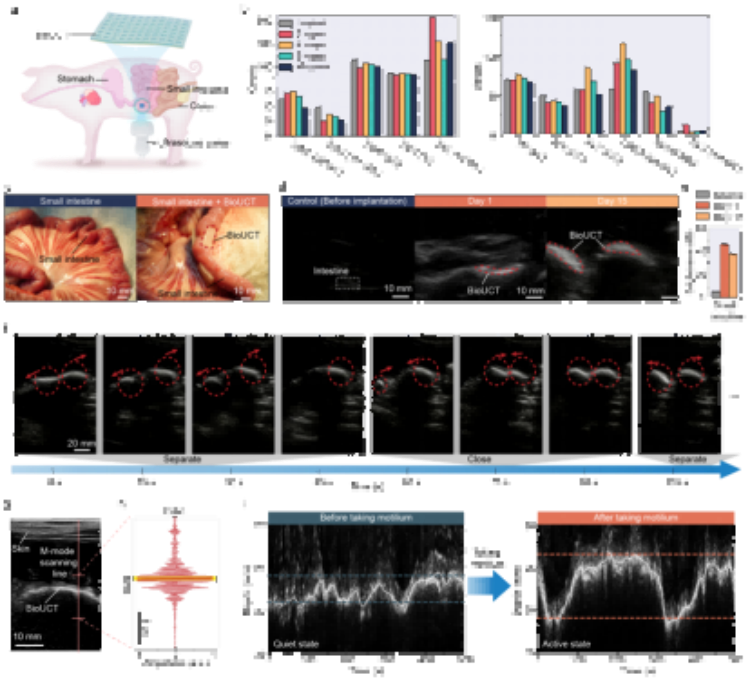

二、應(yīng)用場(chǎng)景

在對(duì)豬腸道蠕動(dòng)幅度監(jiān)測(cè)的驗(yàn)證實(shí)驗(yàn)中,操作人員通過臨床通用的超聲成像設(shè)備成功追蹤到服藥前后腸蠕動(dòng)幅度的變化(3.13mm→7.59mm)。該技術(shù)未來可結(jié)合可穿戴超聲設(shè)備,實(shí)現(xiàn)患者居家監(jiān)測(cè),特別適用于:小腸切除術(shù)后并發(fā)癥預(yù)警慢性腸梗阻患者長(zhǎng)期管理胃腸動(dòng)力藥效評(píng)估。

圖5. 通過BioUCT進(jìn)行活體動(dòng)物腸道運(yùn)動(dòng)監(jiān)測(cè)。